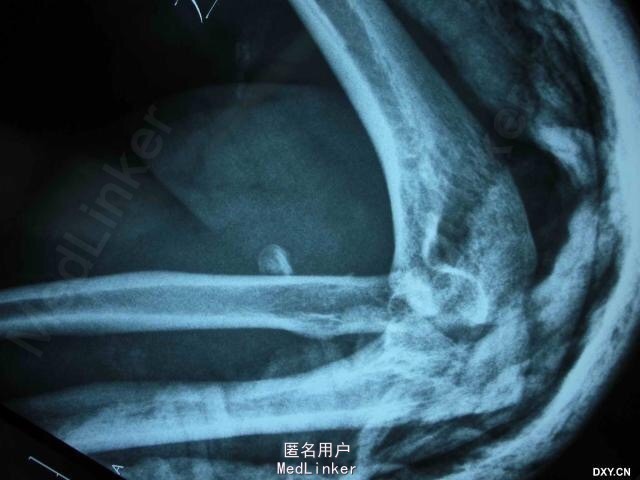

男,45岁,因高处跌落致左肘关节畸形、肿痛、活动障碍 3 天入院。伤后在外院行手法复位后来我院进一步诊治。体检:左肘关节肿胀明显,活动受限。无神经血管并发症。初步诊断:左肘关节损伤三联征。

术前X片